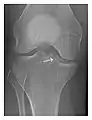

Figure 3: A 26-year-old man presenting with wrist pain after being assaulted. (a) Initial anteroposterior radiograph shows a subtle linear lucency within the scaphoid extending to the scaphocapitate articular surface that was overlooked (arrow). (b) Initial "scaphoid" view was negative. (c) Followup anteroposterior radiographs, 12 days later, shows obvious scaphoid fracture (arrows).[1]